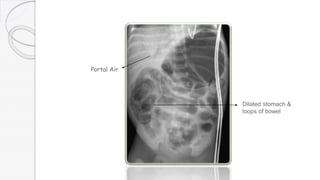

Portal Air

Dilated stomach &

loops of bowel